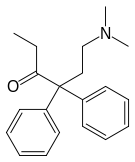

Open chain opioids

Amidones

- Dextromethadone

- Dipipanone

- Isomethadone=

- Levoisomethadone

- Levomethadone

- Methadone

- Methadone intermediate

- Normethadone

- Norpipanone

- Phenadoxone (heptazone)

Structures